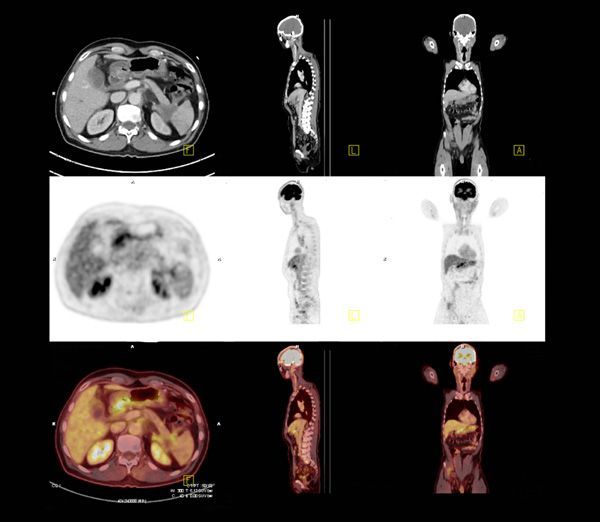

希林さんのように"がん"と付き合うコツ5